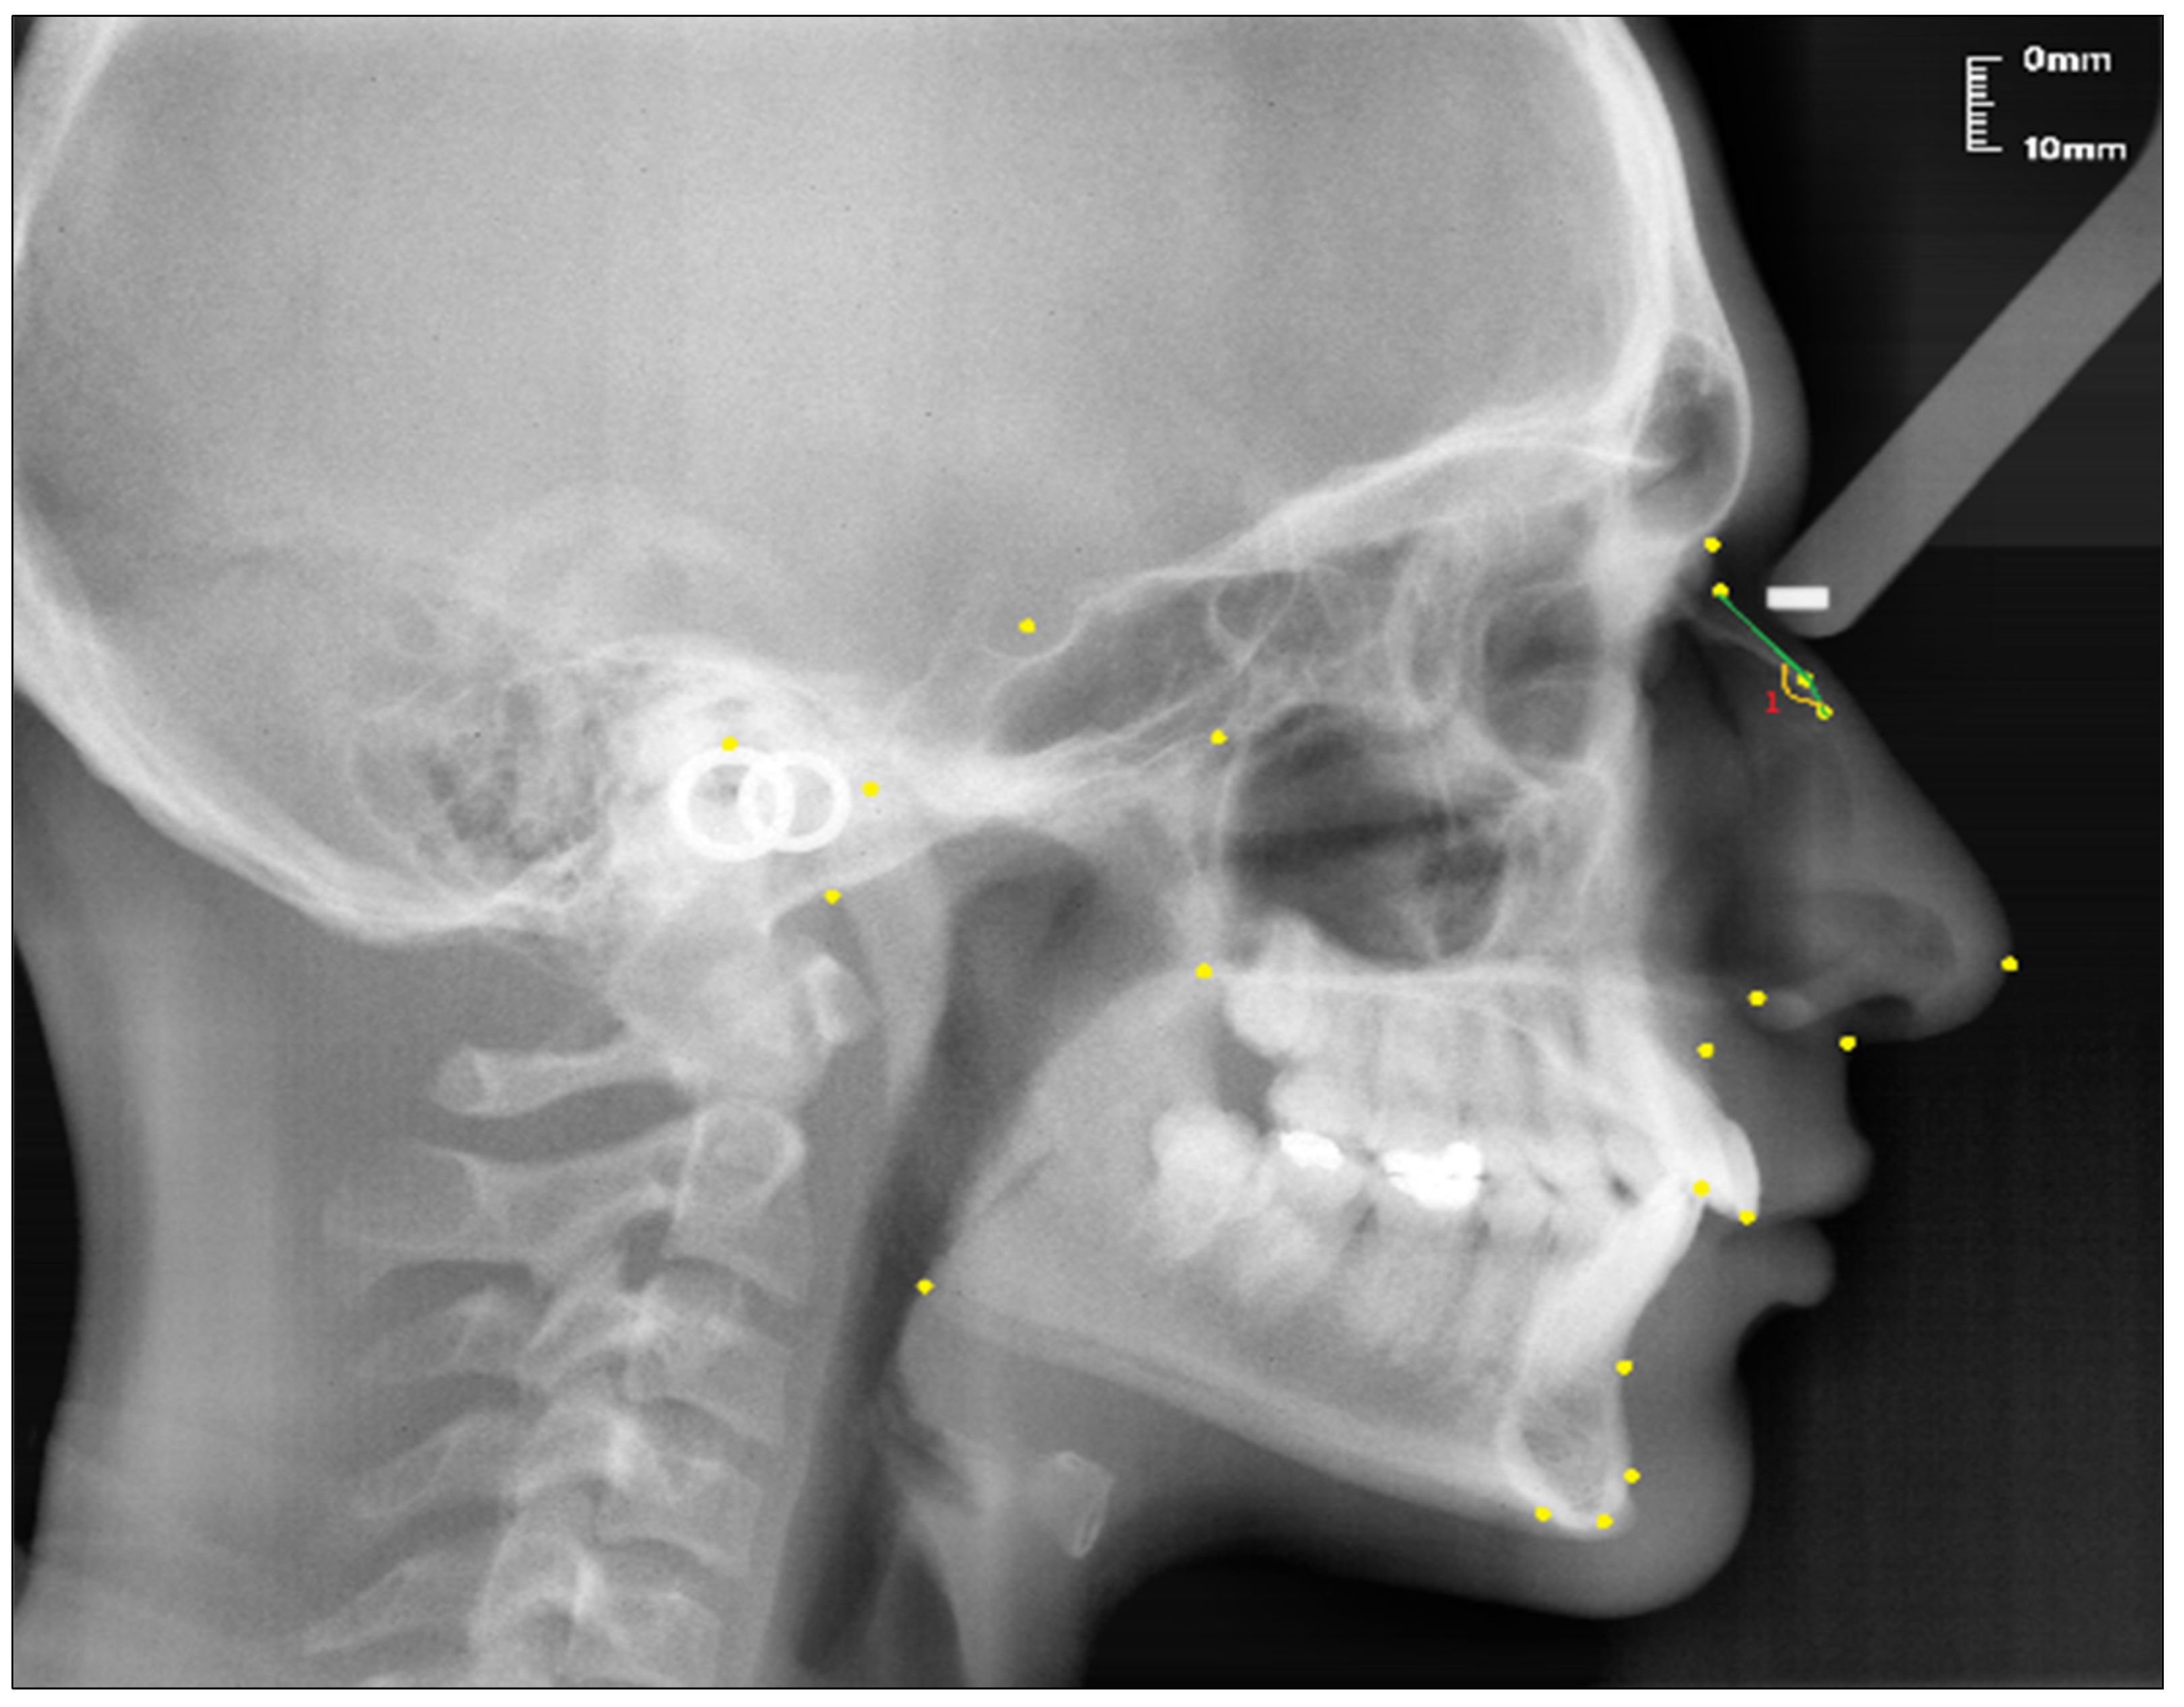

Angular measurement (see Figure 3):

Figure 3.

Angular measurement of the nasal bone used in the study.

- Nasal Bone Concavity Angle (Nbone Angle); the posterior angle formed between the N1-N2 line and the N2-R line.